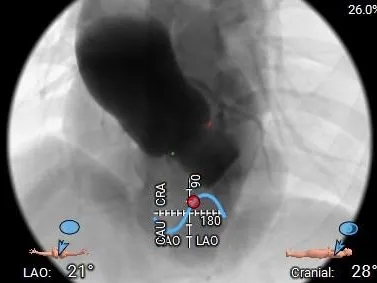

工作体位

双窦展开

左冠切线